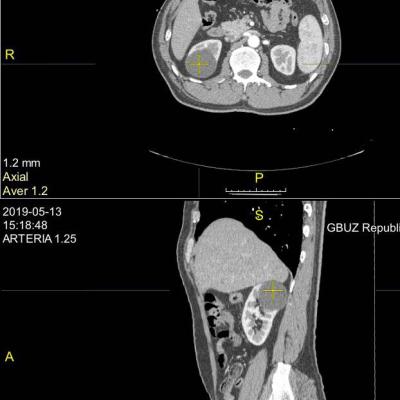

Киста почки.

Киста почки 55 мм (одиночная), медленно растет,

что лучше, с точки зрения надежности и влияния на функцию почки: пункция со склерзированием или лапароскопия.

Здравствуйте! Судя по расположению, безопаснее совершенно точно - пункционная аспирация под УЗ-контролем со склерозированием( под местной анестезией). На функцию почки, при отсутствии осложнений, не повлияет ни один из методов. Удачи!